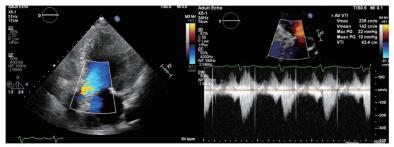

(1)经食道超声评估瓣环、窦、冠脉高度和升主动脉由于患者术前无法行CT检查,无法获知其主动脉根部情况,术中通过食道超声(2D和3D)评估主动脉根部结构。本病例术中经食道超声评估提示:主动脉瓣瓣环内径2.11 cm,主动脉窦部直径2.89 cm×2.84 cm×2.84 cm,右冠开口高度1.12 cm,左冠开口开口1.05 cm,升主动脉无明显增宽(图 3)。

| 图 3 患者术中经食道超声心动图 |